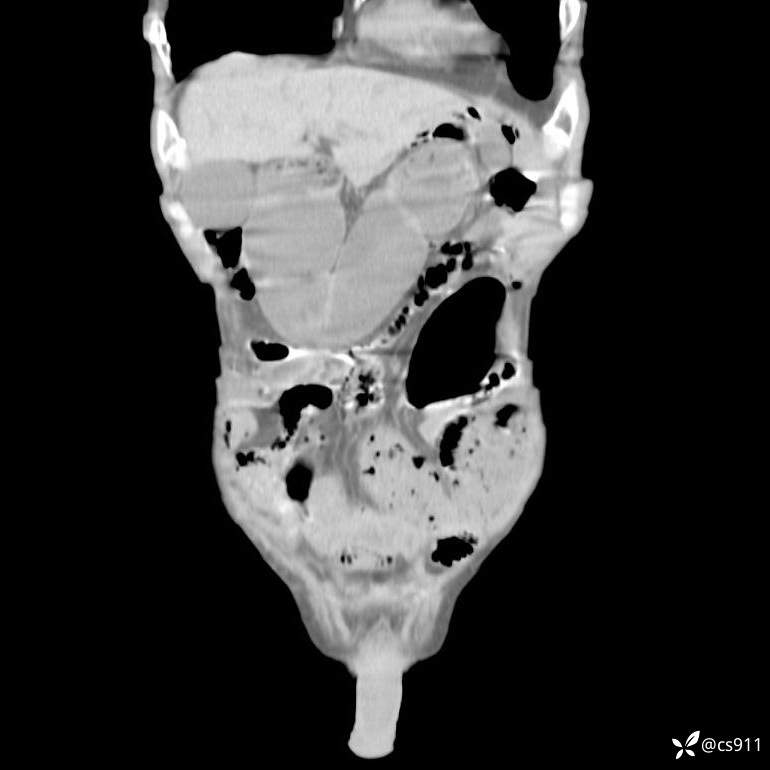

急腹症之急诊CT,原因?答案公布

男,77岁,腹痛、腹胀伴恶心呕吐1天。呕吐胃内容物,非喷射性呕吐,有咖啡色样胃内容物,诉有胃穿孔病史。查体:全腹平,下腹部压痛,全腹无反跳痛,叩诊呈浊音,移动性浊音阴性,肠鸣音减弱,1-2次/分。肛检:直肠未扪及明显肿物,可触及大量粪块。

T 36.6℃ P 80次/分 R 26次/分 BP 100/60mmHg

白细胞(WBC) H 14.55 10e9/L 4-10

中性粒细胞百分率(NEUT%) H 85.7 % 40-75

血淀粉酶(AMY) HH 1859 U/L 35-135

癌胚抗原(CEA) H 27.44 ng/ml 0-5

呕吐物 潜血试验 * 阳性 阴性

患者轮椅入室检查神志清楚, 能配合摆位和呼吸